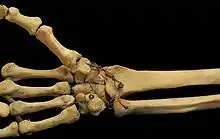

Carpal bones of the hand:

- Proximal: A=Scaphoid, B=Lunate, C=Triquetrum, D=Pisiform

- Distal: E=Trapezium, F=Trapezoid, G=Capitate, H=Hamate

In the hand proper a total of 13 bones form part of the wrist: eight carpal bones—scaphoid, lunate, triquetral, pisiform, trapezium, trapezoid, capitate, and hamate— and five metacarpal bones—the first, second, third, fourth, and fifth metacarpal bones.[8]